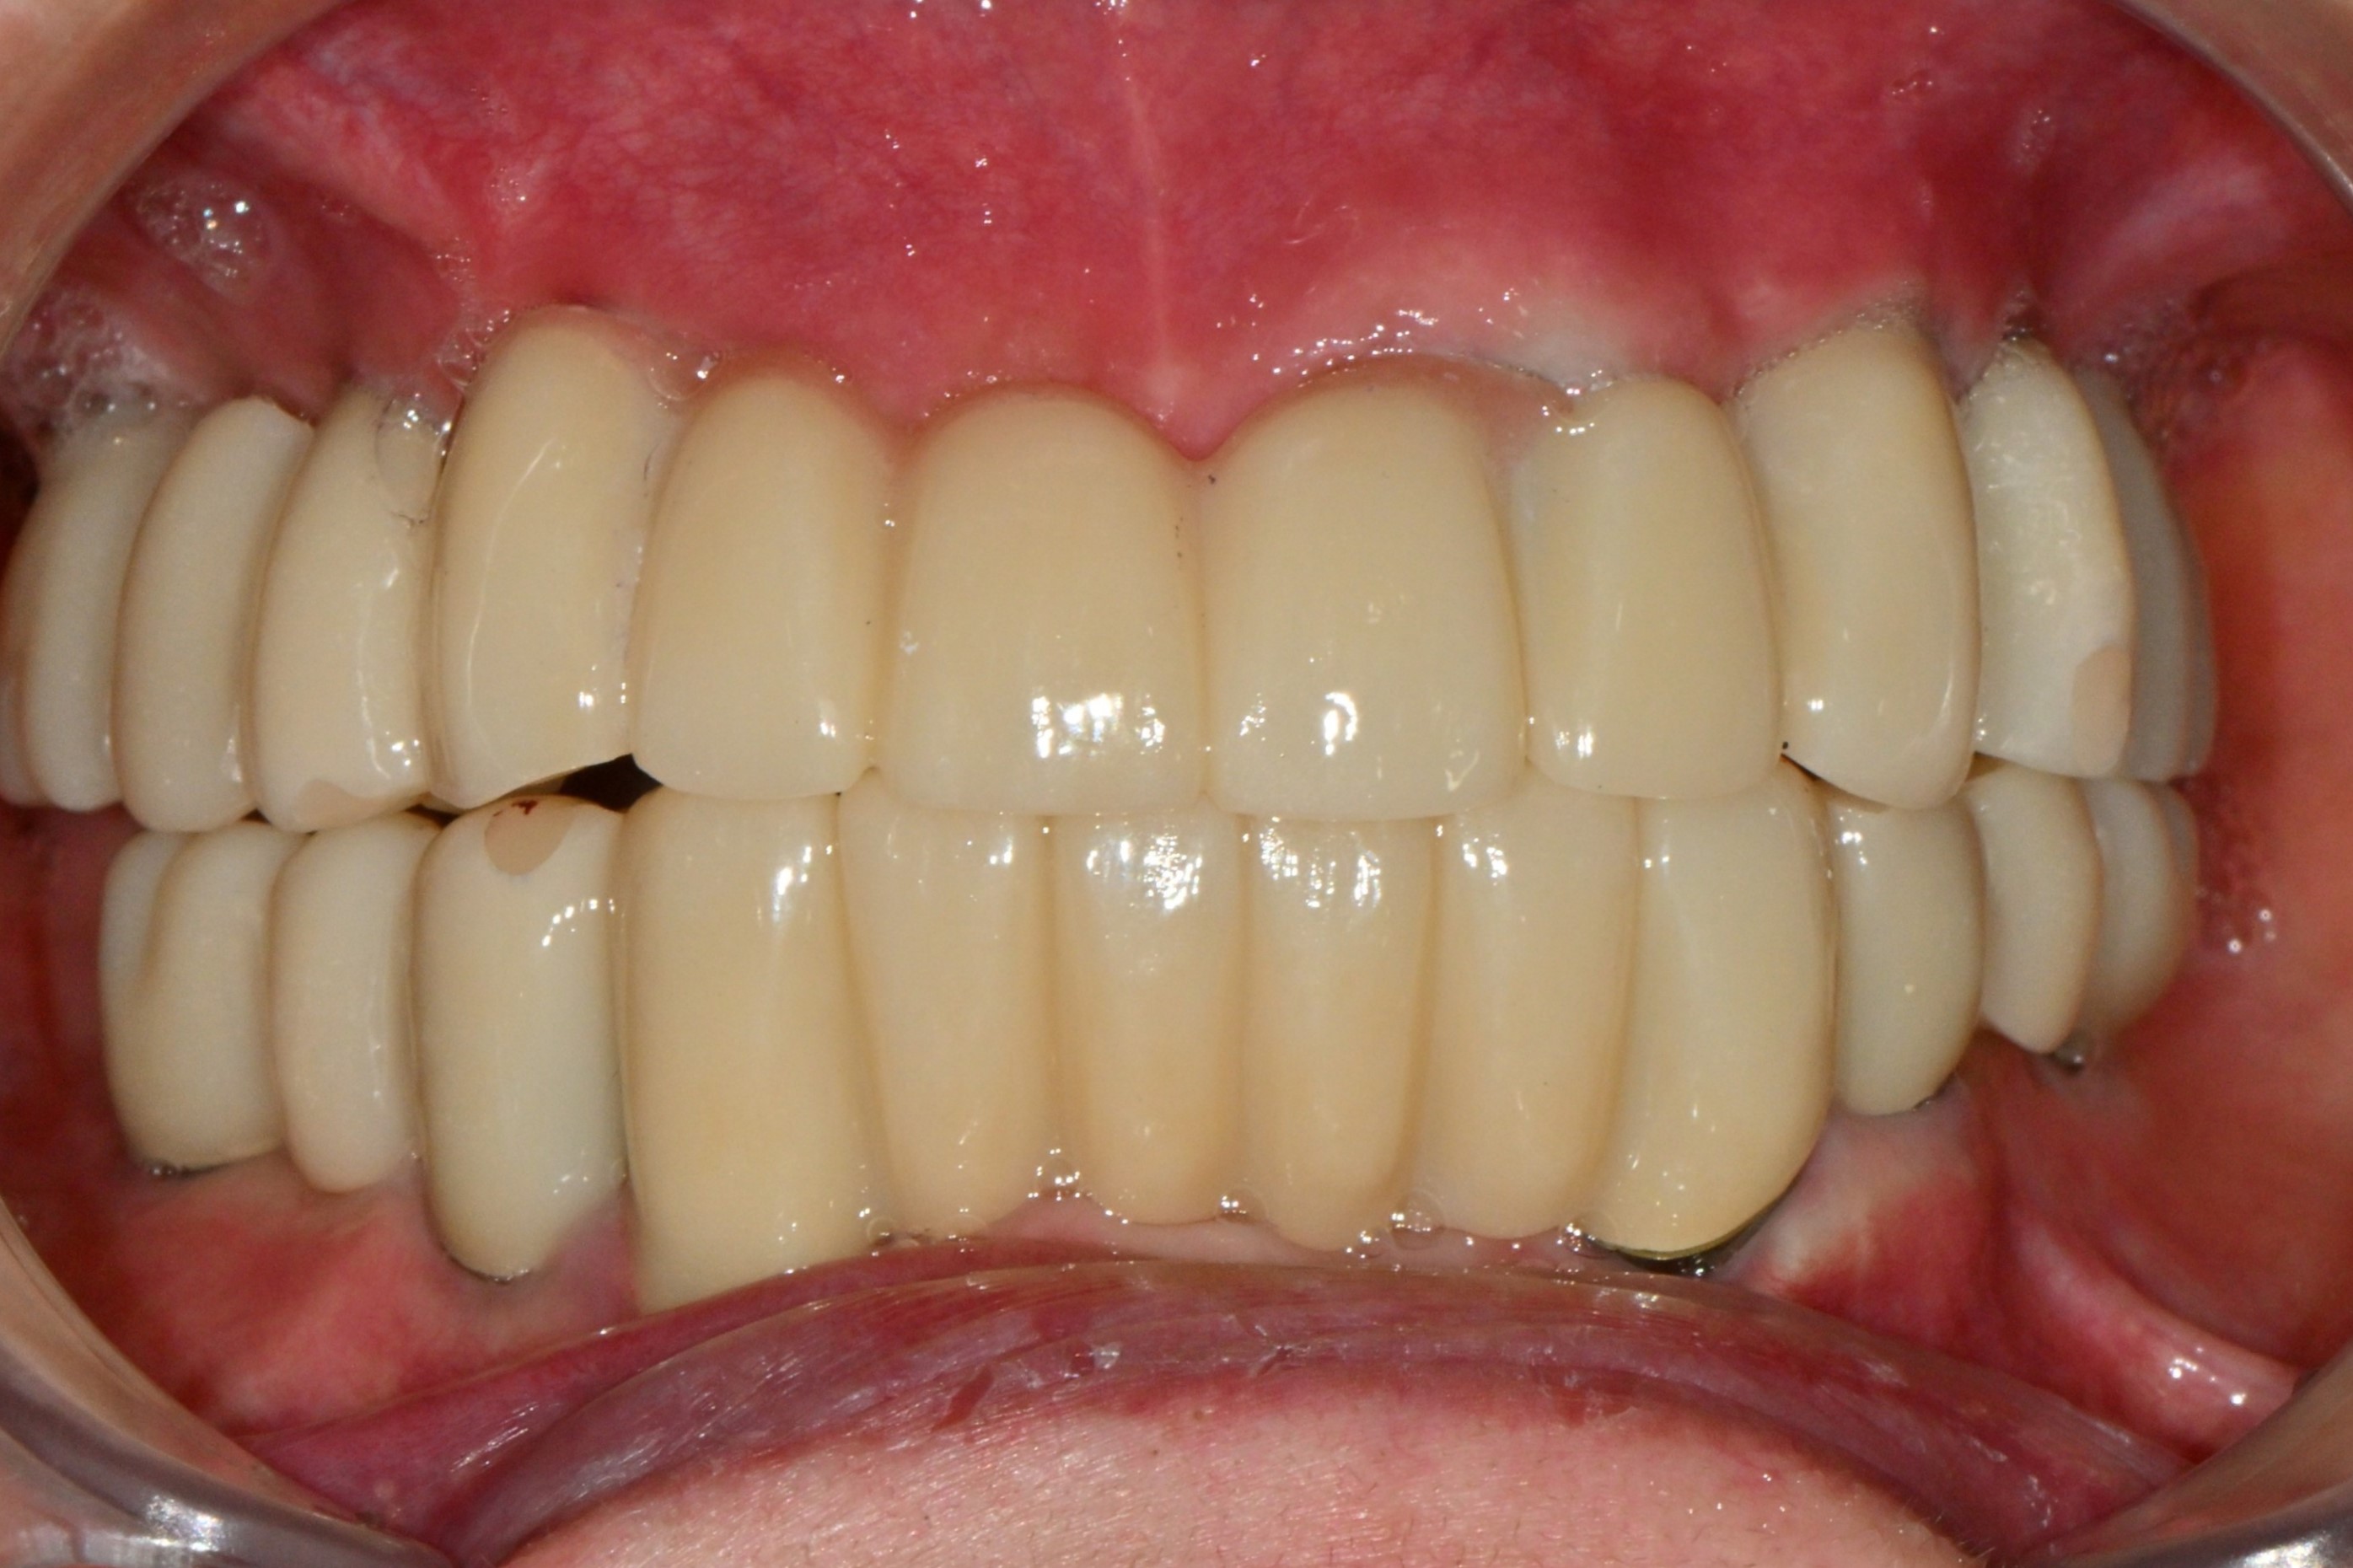

촬영일시: 2025.06.05

촬영일시: 2025.12.31 [ 치료기간: 2025년 06월 05일 ~2025년 12월 31일 ] ※ 365서울앞선치과의원의 모든 컬럼은 각 진료과 의료진이 직접 작성합니다. 365서울앞선치과의원 임상 케이스 게시물은 환자분께 의학적으로 정확하고 상세한 정보를 드리기 위해 각 진료과 의료진이 직접 작성하며, 모든 증례 사진은 본원 의료진이 직접 시술한 증례를 촬영한 것으로, 의료법 제23조, 제56조에 의거하며 환자분의 동의를 얻어 포스팅에 사용하였습니다. 또한 해당 케이스는 본 환자분의 치료 결과이며, 환자 상태에 따라 치료의 결과는 달라질 수 있습니다. |